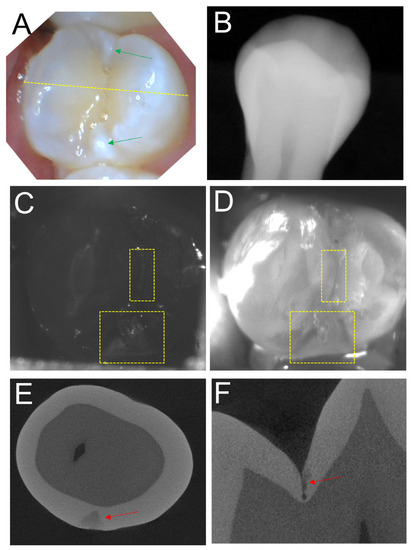

Images from a second tooth from the study are shown in Figure 3. The color image in Figure 3A shows a bicuspid with hypomineralization and areas of high reflectivity near the mesial and distal surfaces indicated by the green arrows. No lesions are obvious in the radiograph in Figure 3B. Only one of the three clinical examiners detected the proximal lesion on the distal surface in the radiograph and none identified it by visual assessment. The SWIR occlusal transillumination and reflectance images acquired with the dual probe are shown in Figure 3C,D and both images show occlusal and proximal lesions in the positions of the yellow boxes. MicroCT images in Figure 3E,F show that lesions are present in the same areas of the yellow boxes. It is interesting that the bright areas in the color image of Figure 3A do not correspond to lesion areas. It is likely they are due to hypomineralization. The SWIR reflectance image in Figure 3C shows the triangular-shaped lesion at the distal contact matching the microCT image and shows no increased reflectivity at the mesial contact.

Figure 3. Images of a tooth with lesions on the occlusal and distal proximal surfaces The color image in (A) shows several bright areas of high reflectivity near the mesial and distal surfaces indicated by the green arrows that may be due to proximal lesions or hypomineralization. No lesions are visible in the radiograph in (B). SWIR reflectance (C) and occlusal transillumination (D) images show occlusal and proximal lesions in the positions of the yellow boxes. MicroCT images show lesions on the distal proximal surface (E) and the occlusal (F) surface as indicated by the red arrows.